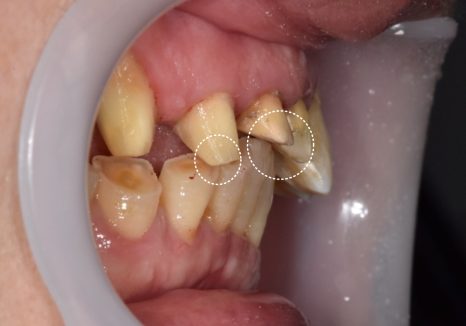

유독 길게 제작된 위 앞니가

아랫니를 계속 건드리면서,

아랫니 속살(상아질)이 비칠 만큼

심하게 마모되어 있었습니다.

아랫니가 닳아 키가 작아지다 보니,

상대적으로 윗니는 더 들쑥날쑥하고

삐뚤어 보일 수밖에 없었죠.

아랫니가 이미 많이 닳아

낮아진 상태라,

위 앞니 배열을 반듯하게 맞추면

특정 부위가 아랫니와 맞물리지 않고

살짝 뜨게 되는 구조였거든요.

230711

저는 이 부분을 환자분께

솔직하게 설명드렸습니다.

다행히 환자분께서도

"어금니로 잘 씹히면 되니,

이번엔 꼭 예쁜 앞니를 갖고 싶다"고

동의해주셔서

미관에 초점을 맞춘 디자인을 진행했습니다.

또한, 환자분의 씹는 힘(교합력)이 매우 강해

일반 도자기는 깨질 위험이 컸습니다.

그래서 강도가 월등히 높은

'지르코니아'를 선택해

튼튼함까지 놓치지 않았습니다.